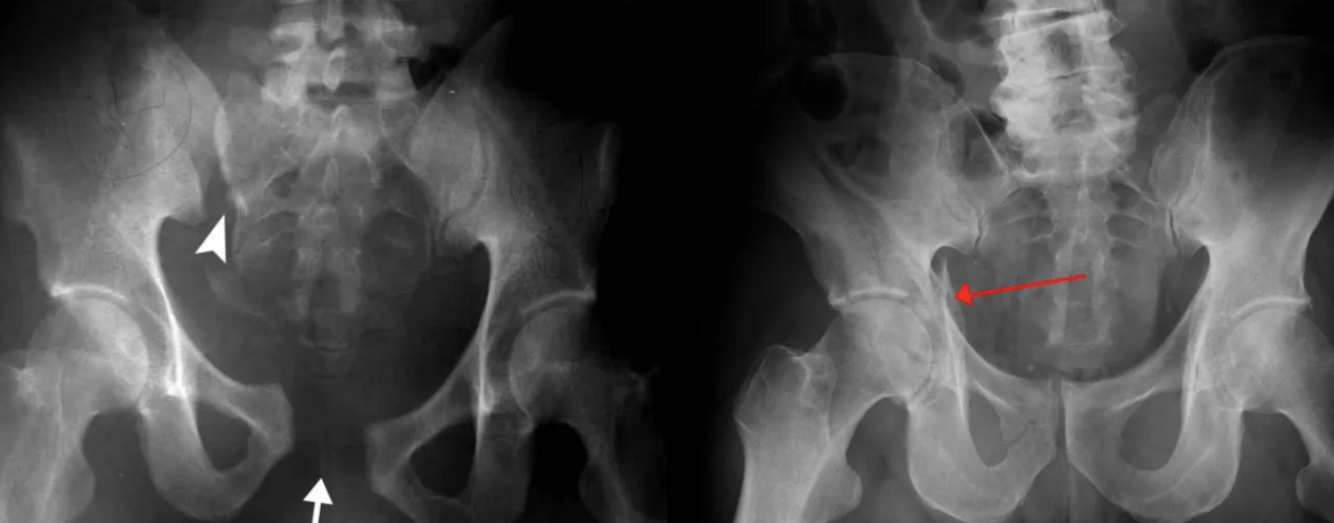

What are the pathologies in this picture?

What are the pathologies present in this picture?